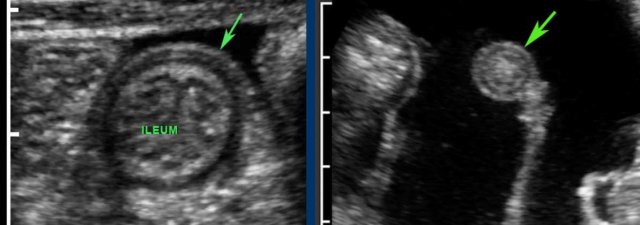

Note the lymphoid hyperplasia of the Peyer’s patches in the terminal ileum.

These are images of the terminal ileum in three different children and young adults with large Peyer’s patches presenting as asymmetrical, hypoechoic thickening of the deep mucosa.

With every new antigen, the lymphoid tissue becomes reactivated.

In young patients both mesenteric lymph nodes and Peyer’s patches are –also in absolute dimensions- much larger than in adults.

The stimulated lymphoid tissue in youngsters not only results in prominent Peyer’s patches in the terminal ileum and enlarged mesenteric lymph nodes (left under), but also in a thickened deep mucosa of the appendix (right under).

Note that the –sometimes polyp-like- protrusions (right upper), may act as lead-point in the classic ileocecal intussusception in young children